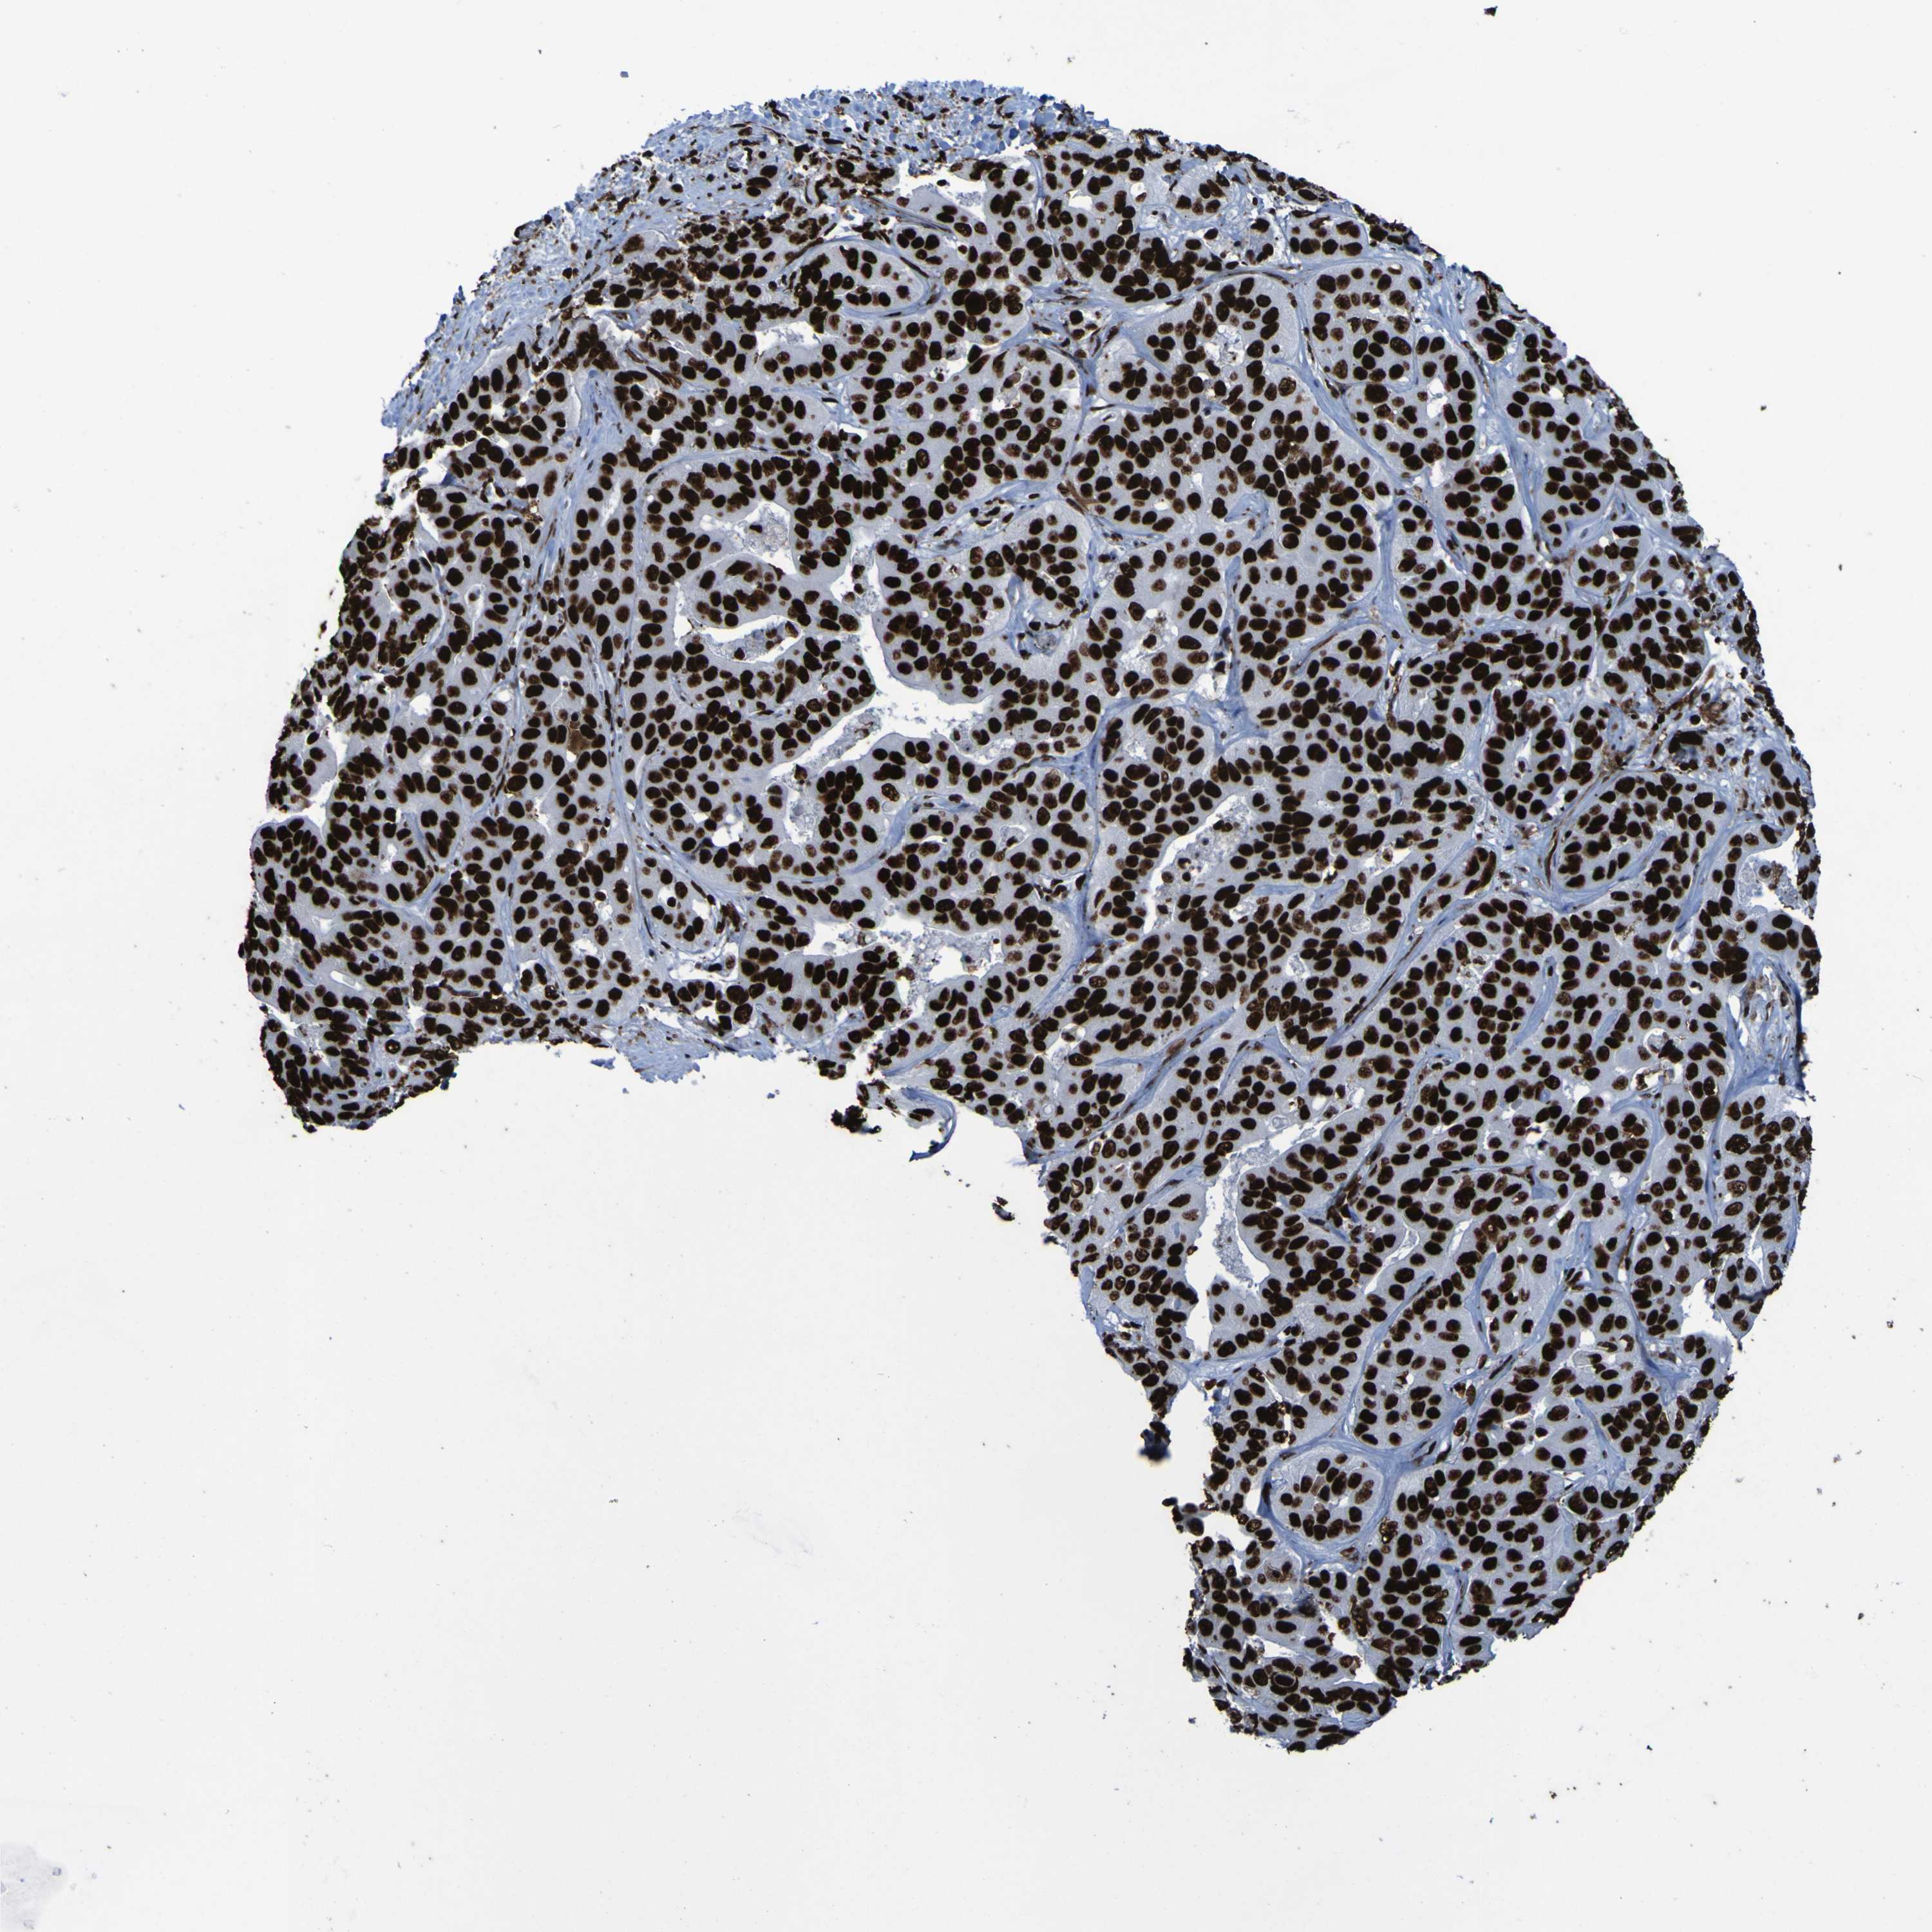

LIVER CANCER - Protein expressioni

A mouse-over function shows sample information and annotation data. Click on an image to view it in a full screen mode. Samples can be filtered based on level of antibody staining by selecting one or several of the following categories: high, medium, low and not detected. The assay and annotation is described here.

Antibody stainingi

Antibody staining in the annotated cell types in the current human tissue is reported as not detected, low, medium, or high, based on conventional immunohistochemistry profiling in selected tissues. This score is based on the combination of the staining intensity and fraction of stained cells.

Each image is clickable and will lead to virtual microscopy that enables deeper exploration of all samples and also displays staining intensity scores, fraction scores and subcellular localization as well as patient and tissue information for each sample.

Antibody HPA011384

Staining

High

Intensity

Strong

Quantity

>75%

Location

Nuclear

Carcinoma, Hepatocellular, NOS